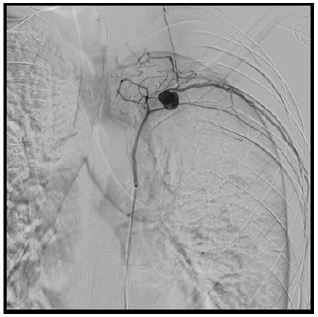

The patient underwent superselective arterial embolization of the involved intercostal artery (Figure 1). The procedure was successfully performed using microcoils (3 and 4 mm), obtaining immediate stop of bleeding (Figure 2). A left chest tube was placed and 1200 mL of blood were evacuated. The patient then underwent videothoracoscopic debridement to evacuate clots and some retained blood.

Figure 1: Angiographical embolization of intercostal pseudoaneurysm using microcoils.